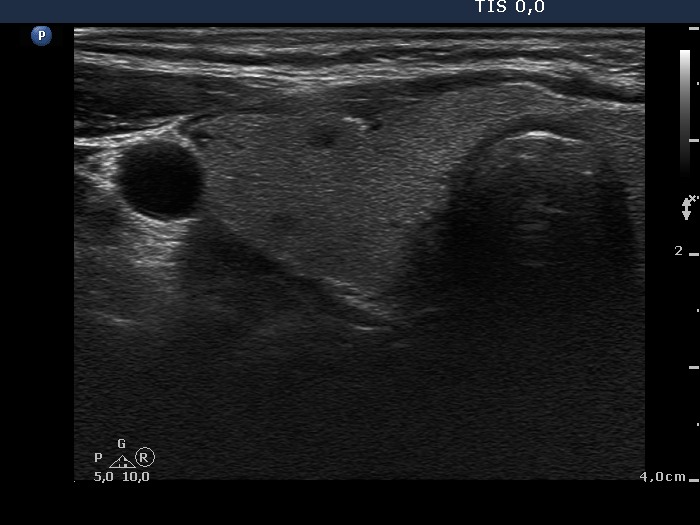

Ultrasonography: the thyroids were echonormal. There was a small hypoechogenic lesion in the ventral part of the right lobe, while a large hyperechogenic nodule presenting a halo sign and perinodular blood flow in the left thyroid. The size of the nodule increased from 25x19x27 mm to 30x27x33 mm (width, depth, length, respectively).